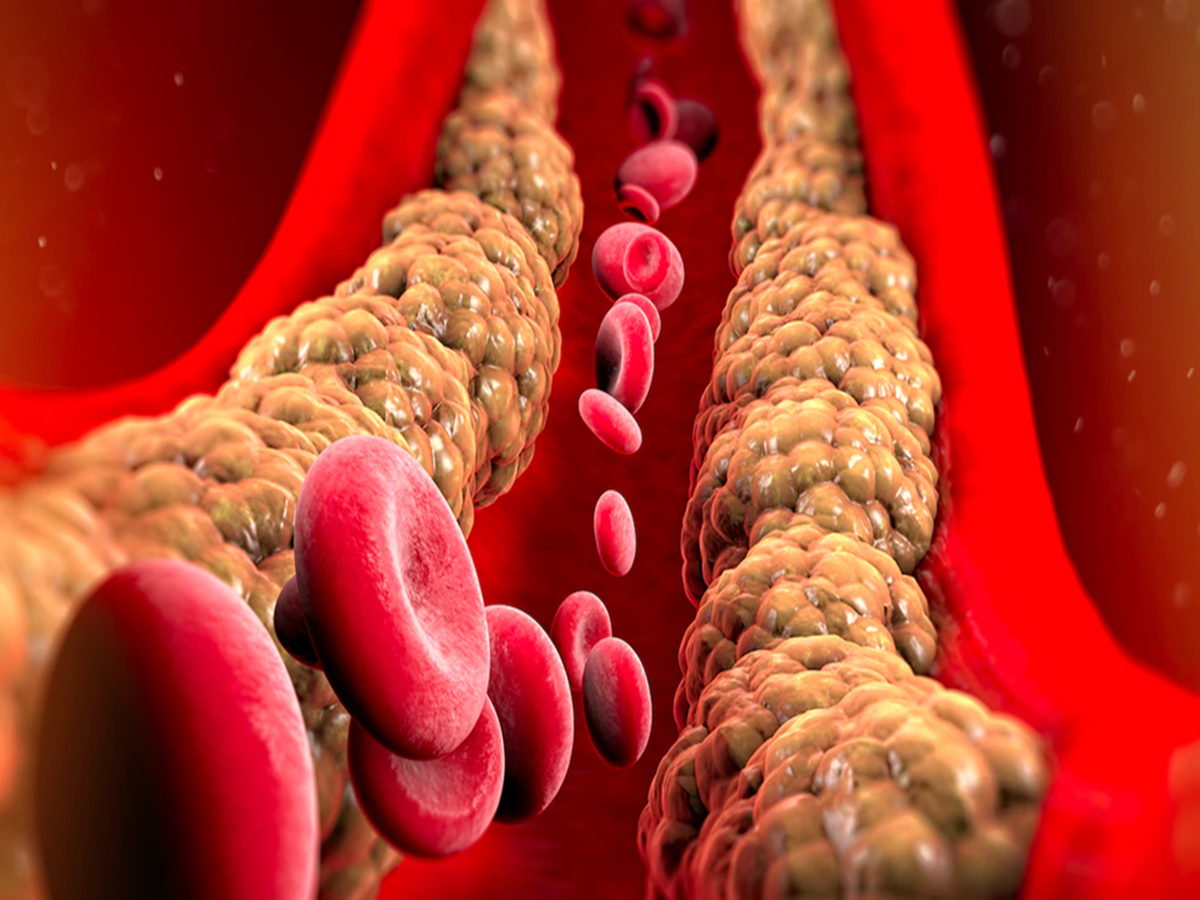

High cholesterol is a major cause of heart attacks and heart disease, but it's often called the silent killer. It gets this name because the signs of high cholesterol don't appear until the situation becomes very serious.

Cholesterol is a waxy substance found in our blood. The body needs a certain amount of good cholesterol (HDL), but if the amount of bad cholesterol increases, it starts accumulating in the arteries.

Plaque buildup - When the amount of bad cholesterol in the blood is high, it begins to stick to the walls of the arteries. Over time, it hardens and forms plaque.

Narrowing of the arteries - As plaque builds up, the arteries become narrower and stiffer. This reduces blood flow and increases blood pressure.

Blocked blood circulation - This process can occur painlessly for years. The body adapts to this change, so the patient may not feel anything.

Heart attack or stroke - When arteries become completely blocked or there is very little room for blood flow, it causes a heart attack or stroke.